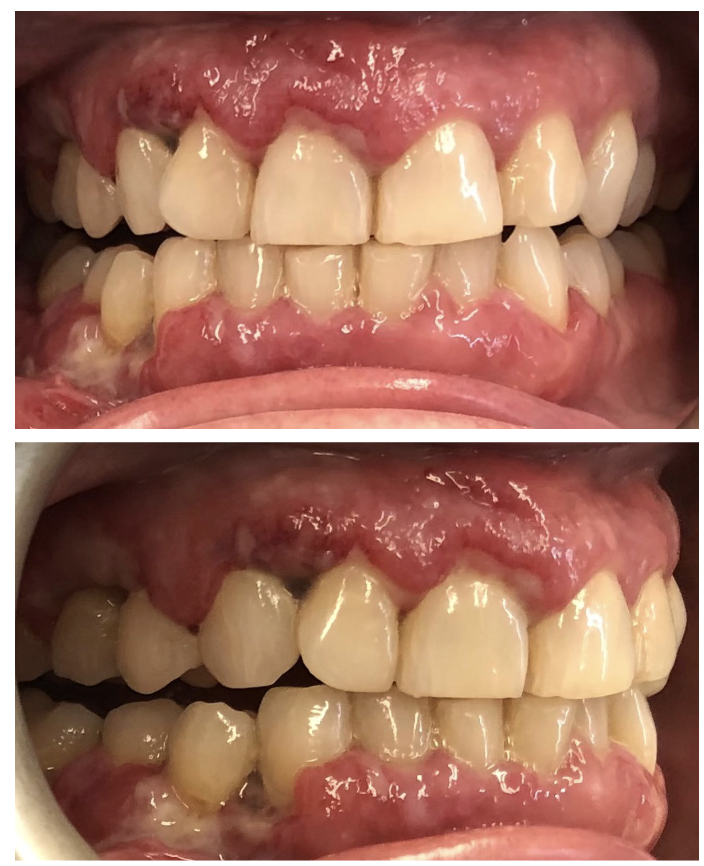

Diffuse, boggy, non-tender swelling of gingiva. With or without ulceration

Leukemia

Clinical Presentation:

Enlarging, nontender discrete mass in lymph node region

Pruritis (itchiness)

Oral nontender diffuse soft tissue swelling

Lymphoma

Most common oral sites for lymphoma lesions?

Buccal vestibule, posterior hard palate, gingiva